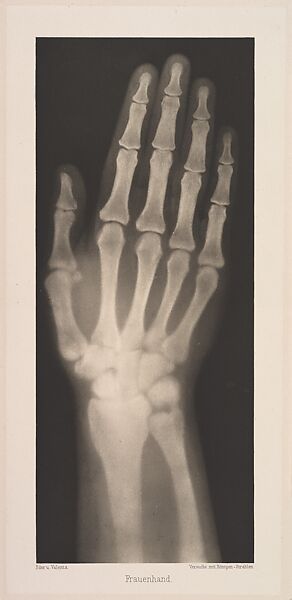

Versuche über Photographie mittelst der Röntgen'schen Strahlen

Eder was the director of an institute for graphic processes and the author of an early history of photography. With the photochemist Valenta, he produced a portfolio in January 1896, less than a month after Wilhelm Conrad Röntgen published his discovery of X-rays. Eder and Valenta’s volume, from which this plate derives, demonstrated the X-ray’s magical ability to reveal the hidden structure of living things. Human hands and feet, fish, frogs, a snake, a chameleon, a lizard, a rat, and a newborn rabbit are all presented in exquisitely printed photo-gravures, as are carved cameos and an assortment of natural materials. In an era when photography’s ability to accurately depict the visible world had become commonplace, this newfound capacity to record the invisible opened up a host of possibilities, both scientific and aesthetic. The careful compositions and shocking appearance of these “Experiments in Photography” link them to the previous century’s tradition of natural-history illustration and point toward the experiments of New Vision photographers in the 1910s and 1920s.

- Title: Versuche über Photographie mittelst der Röntgen'schen Strahlen

- Artist: Josef Maria Eder (Austrian, Krems an der Donau, 1855–1944 Kitzbühel) and

- Artist:  Eduard Valenta (Austrian, 1857–1937)

- Date: 1896

- Medium: Photogravures